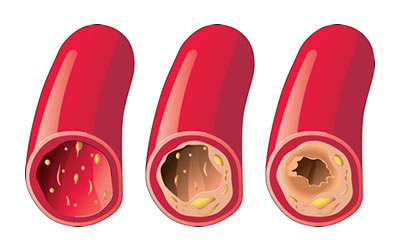

H αθηροσκλήρωση είναι μία χρόνια πάθηση στην οποία εμφανίζεται βλάβη των μεγάλων και μεσαίων αρτηριών, από τα λιπίδια που παρουσιάζονται στα τοιχώματά τους. Τα λιπίδια (ένα από αυτά είναι η «κακή»-LDL χοληστερόλη) βρίσκονται στο αίμα και με τα χρόνια κάθονται στα τοιχώματα των αρτηριών, τα οποία στενεύουν.